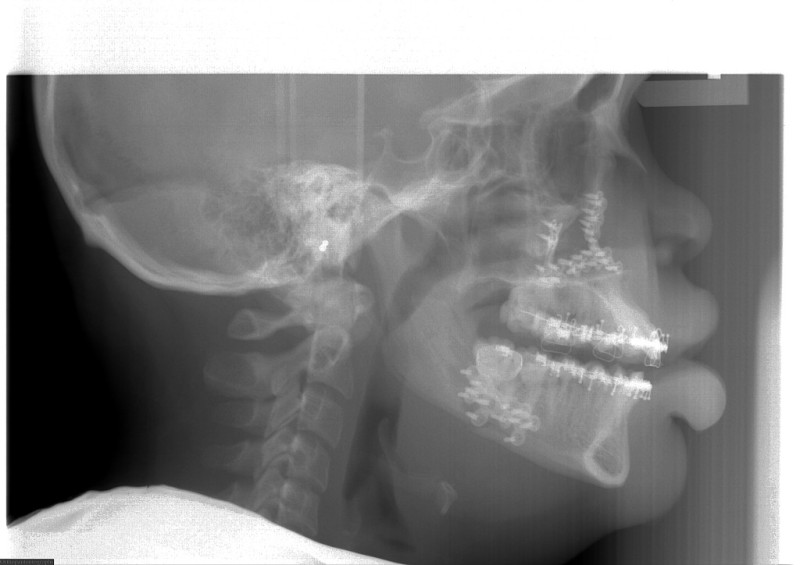

The surgical team spends much time and energy in collaboration with the orthodontist to plan the surgery.  A joint treatment plan is devised.  The orthodontist sets up for the surgery with braces.  The surgical team then plans the surgery using xrays to predict the movements, performs the surgery on models, then fabricates acrylic splints to guide the surgical team in the operating room.

After Orthodontic Setup - Presurgical